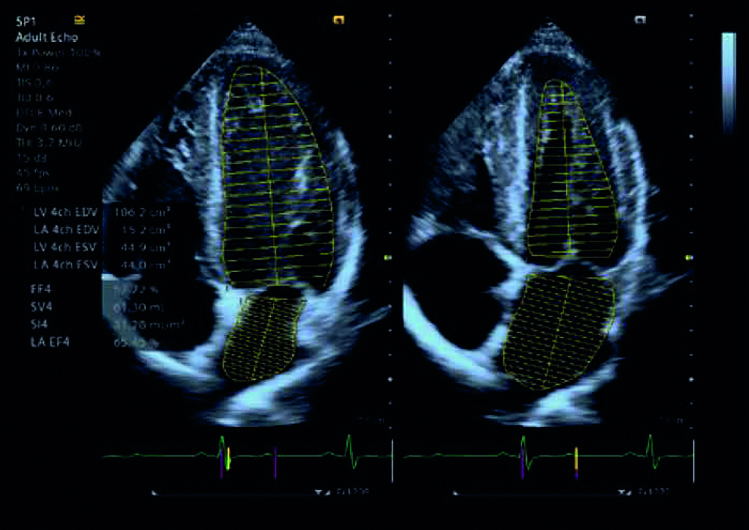

Rileva e misura automaticamente i contorni del ventricolo sinistro e dell’atrio per migliorare il workflow utilizzando eSie Left Heart.